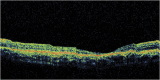

Results: A 6-year-old girl with thalassemia major who was on chronic multiple blood transfusions since 2 years of age presented with blurred vision in both eyes for 2 months. Blood reports showed very high serum ferritin levels in the range 400 to 2,250 ng/mL (checked every 3 months) since 4 years of age. She was on oral iron chelator deferasirox for 2 years, which was stopped a month ago. Fundus examination of both eyes showed a characteristic bull's eye macula with a purplish hue in the outer ring probably due to iron deposition. The center of the bull's eye had a beaten bronze appearance.